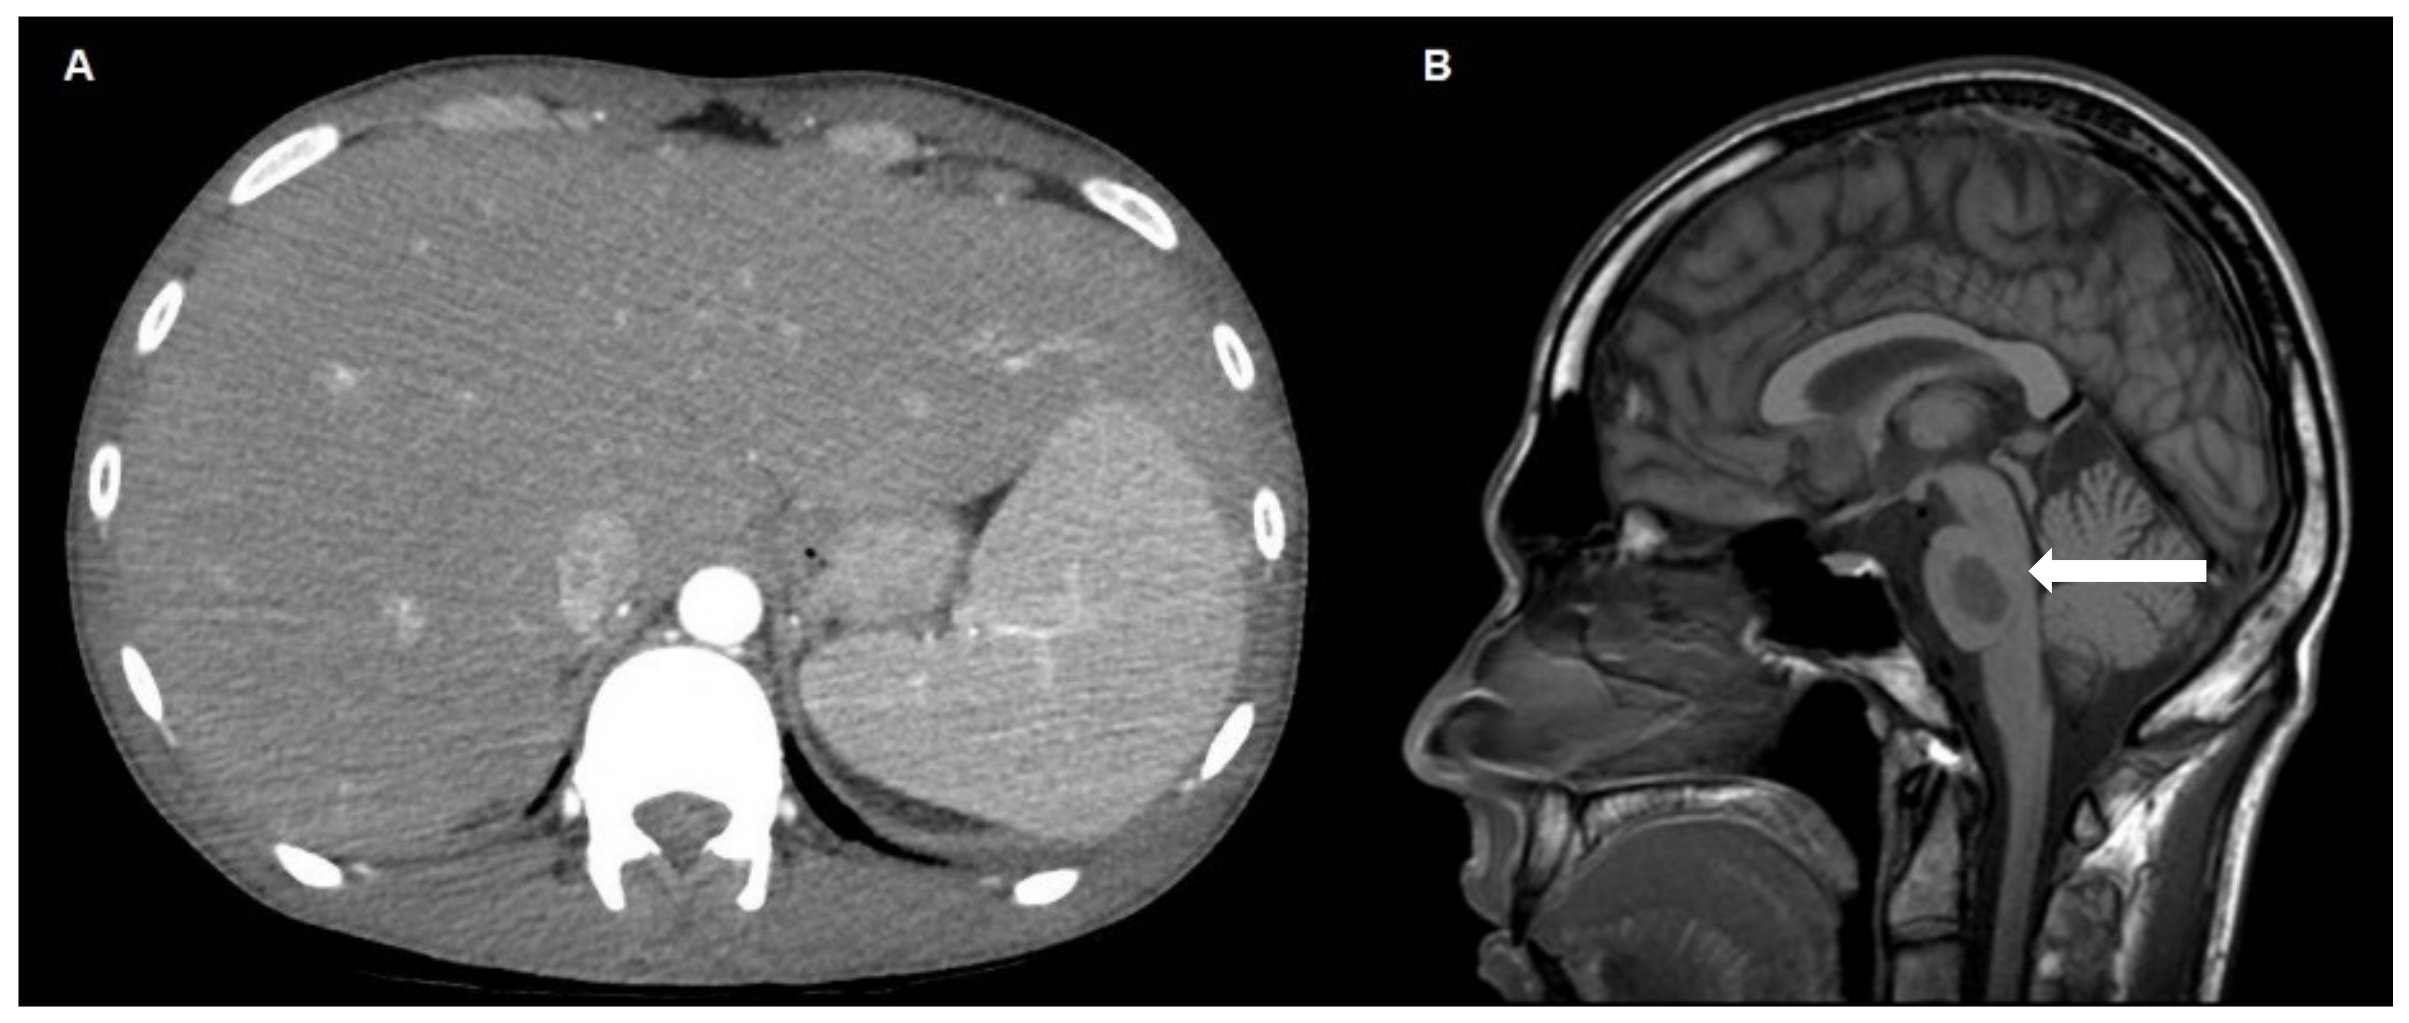

Hepatosplenic T-Cell Lymphoma Mimicking Acute Onset of Cholestatic Hepatitis in a Young Immunocompetent Man: A Case Report

2. Case Report